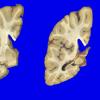

1A1 NCL (Case 1) gross 4

1A4 NCL (Case 1) gross 6